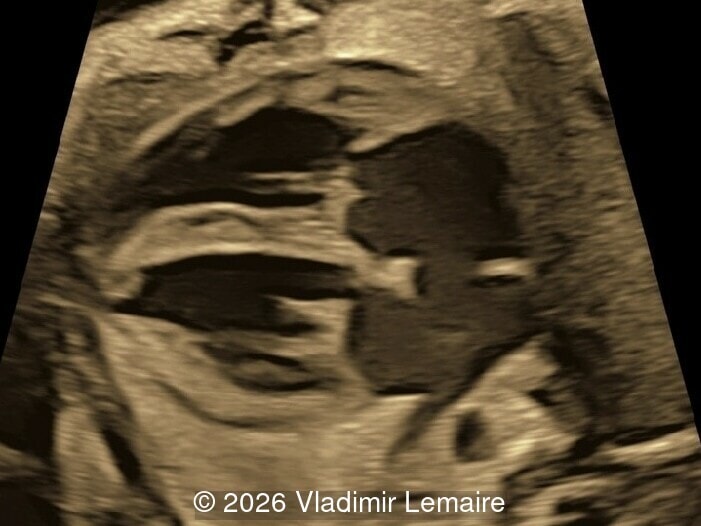

Axial 3D glass-body mode of the intracerebral vasculature.

Image 2 Axial 3D glass-body mode of the intracerebral vasculature.

Our imaging revealed enlargement of the fetal heart with dilation of the superior vena cava. On further evaluation, we identified an elongated anechoic cystic structure in the midline of the head, without mass effect on the surrounding structures. Color doppler demonstrated an arteriovenous fistula between the deep choroidal arteries and the embryonic median prosencephalic vein of Markowski. The vein of Galen aneurysmal malformation was likely the contributing factor to the cardiac enlargement. Cardiac function was, however, preserved and hydrops not present. Additional images are shown below.

On ultrasound, a VGAM appears as an elongated anechoic cystic structure in the middle of the head, often without mass effect on the surrounding structures. Color Doppler shows high-velocity flow in the lesion and can be used to identify the arteries feeding the vascular malformation. Pulsed-wave Doppler shows markedly turbulent flow. Additional key echocardiographic features include an enlarged heart with preserved systolic function, a dilated superior vena cava, and mild or moderate tricuspid regurgitation. Tricuspid regurgitation was not present in our case at the time of our evaluation.